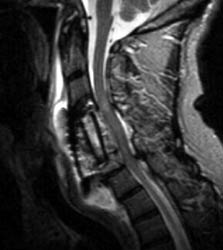

A B C Sagittal T2 FSE (A), sagittal T1 pre (B) and post contrast administration (C) show the graft with blooming artifact where the plate exists anteriorly as well as the screw (lower portion of the image). The susceptibility artifact of the screw shows its ventral positioning essentially outside of the C7 vertebral body. Also, there is T2 hyperintense fluid surrounding the surgical site with the graft material is now surrounded by nonenhancing mixed signal intensity material, predominately hypointense on T1 and hyperintense on T2, possibly suggesting some blood products. There is enhancement in both the anterior and posterior epidural spaces. The distal end of the fixation plate with the screw in the C6 vertebral body appears now displaced anteriorly and there is significant prevertebral soft tissue swelling. Also, this fluid- like material surrounding the bone graft appears to cause some narrowing of the spinal canal, with some mild spinal canal stenosis.